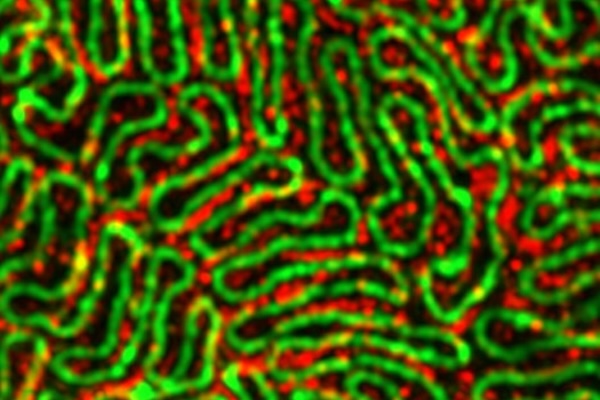

“Podocytes look a bit like octopi that are hugging their neighbors,” said Genin, who is also the co-director of the National Science Foundation Science and Technology Center for Engineering Mechanobiology (CEMB). “When you look at these tentacles with advanced microscopy, the ways that they come together to form the kidney’s filtration system become clear. Without these connections, the entire filtration system falls apart. Everyone is born with a certain number of podocytes. You lose some over time, including a few every time you go to the bathroom, but certain diseases and injuries to the kidneys can cause you to lose them much faster.”

The project leverages expertise across disciplines, with Miner's lab providing knowledge of kidney biology, Suleiman bringing expertise in advanced imaging techniques and cell biology, and Genin contributing knowledge of mechanical forces in living systems. The team will use state-of-the-art imaging, including super-resolution microscopy, to visualize podocyte structure in unprecedented detail. They will also employ techniques to measure and manipulate the mechanical forces on cells.